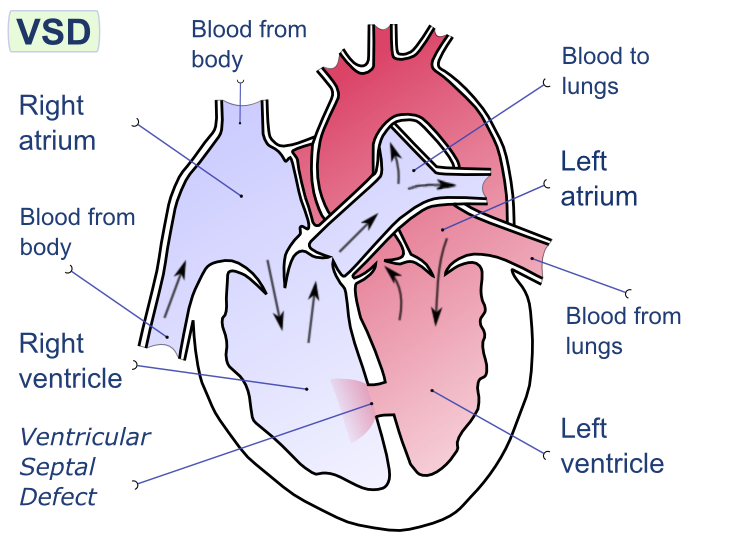

Ventricular Septal Defect (VSD)

A ventricular septal defect is a flaw in the wall that separates the right and left ventricles, or septum.

Ventricular septal defect is the most common congenital cardiac condition.

Ventricular septal defect is inextricably linked to fetal alcohol syndrome.

Ventricular septal defect results in a shunt from left to right.

Age at presentation and defect size both depend on the ventricular septal defect size.

Large ventricular septal defect can cause Eisenmenger syndrome.

Treatment of large ventricular septal defect involves surgery.

Small ventricular septal defects are frequently asymptomatic.

Small flaws might naturally close.